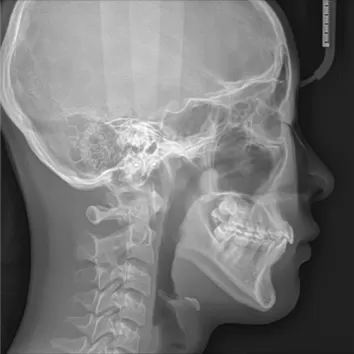

X-rays before treatment

[Panoramic Radiography/Lateral Cephalogram]